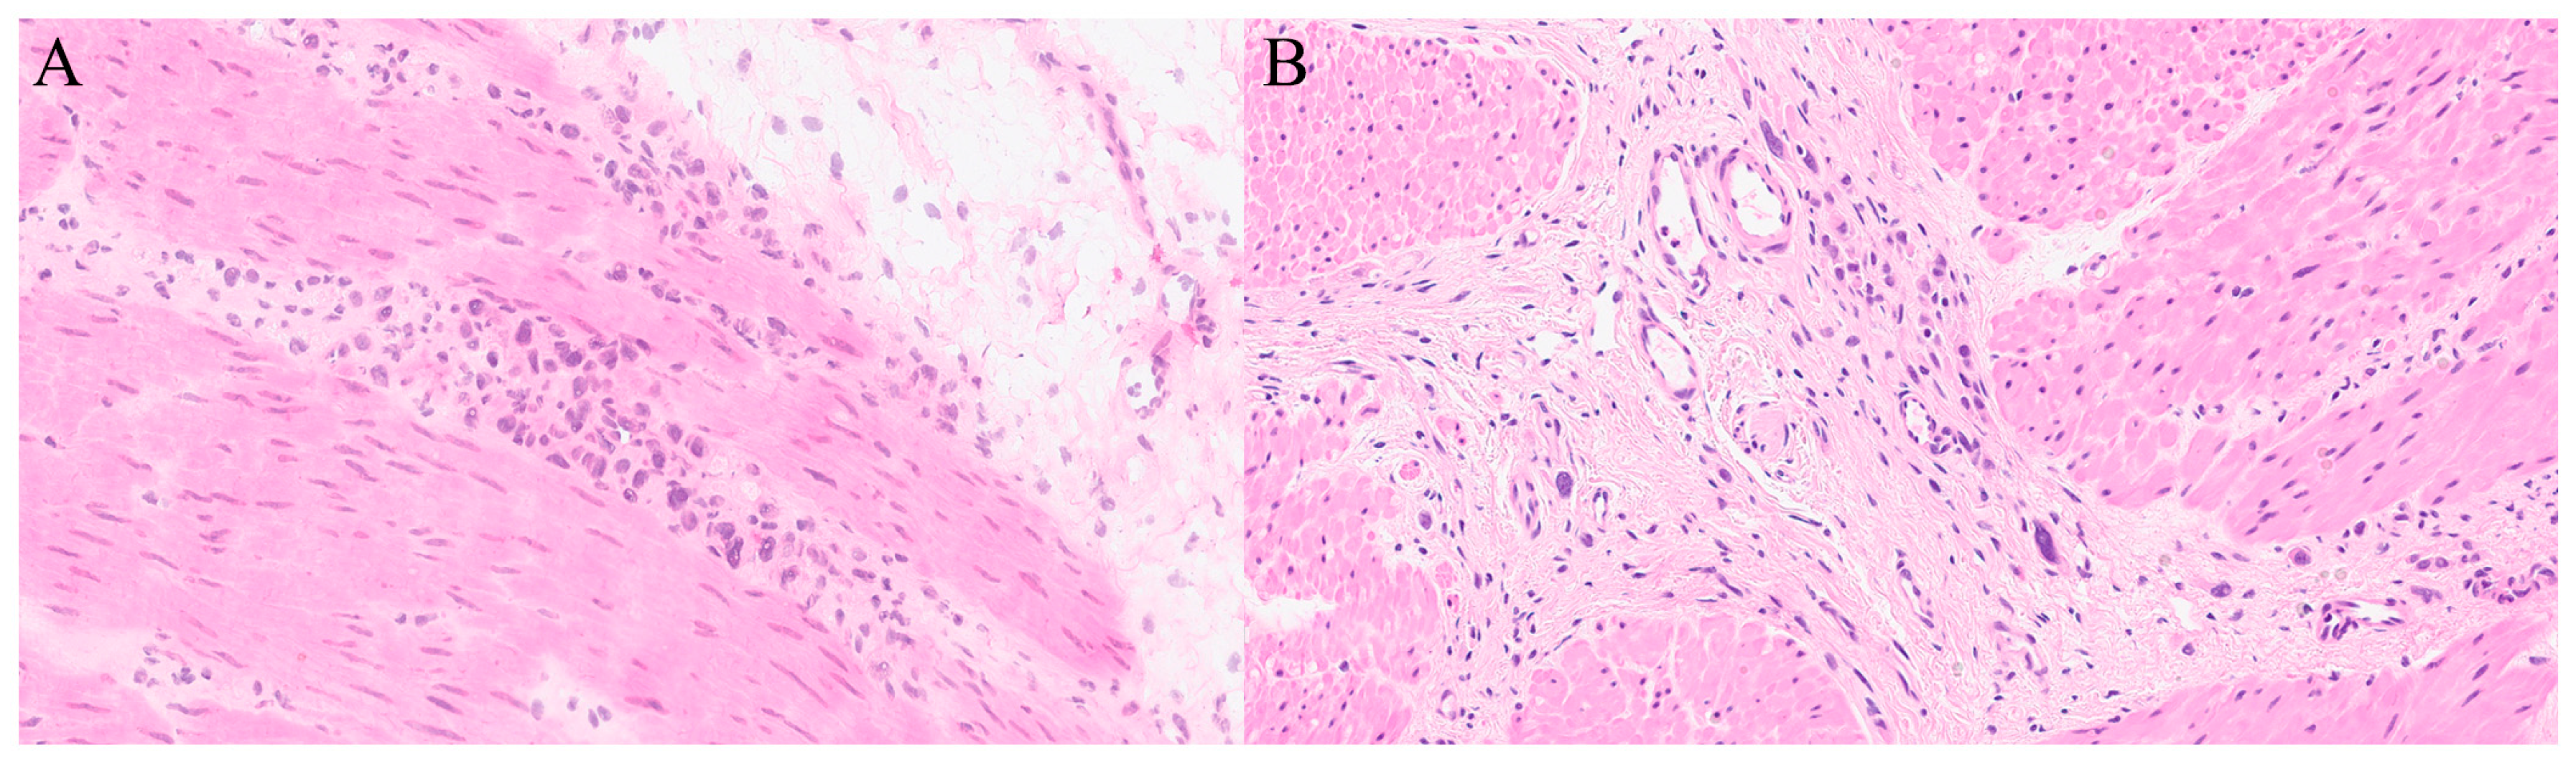

Benign lesions include bile duct adenoma and hamartoma (Table 2). Bile duct hamartomas (von Meyenburg complexes) present as multiple, small, well-circumscribed foci of dilated bile ducts lined by bland cuboidal epithelium within fibrotic stroma, lacking atypia or mitoses [80]. Bile duct adenomas are typically solitary, larger, and composed of tightly packed small ducts with compressed lumina, similarly lined by bland cuboidal cells [80]. Other benign findings may include fibrotic nodules, haemangiomas, biliary or mesothelial cysts, inflammatory nodules, or even normal hepatic tissue [81].

The principal pitfall is misinterpreting bile duct adenoma or hamartoma as metastatic adenocarcinoma, particularly on FS, where freezing artefacts and limited sampling can obscure ductal detail [82,83]. Suspicious regions adjacent to resection margins should be sampled perpendicularly to assess potential tumour extension [63]. Generic limitations such as freezing artefacts and sampling errors that distort hepatic architecture are addressed in Section 19.

Differentiating well-differentiated HCC from regenerative nodules or focal nodular hyperplasia, and cholangiocarcinoma from reactive biliary proliferations, remains among the most challenging aspects of hepatic FS [82]. Both under- and over-diagnosis can occur: HCC may resemble regenerative change, whereas reactive ductular proliferation in chronic inflammation may mimic carcinoma.

The underlying reason FS interpretation often fails in liver surgery lies in the organ’s architectural and reactive complexity [80,82]. Fibrosis, inflammation, and post-therapy effects distort lobular structure and induce ductular reactions that imitate metastatic adenocarcinoma or cholangiocarcinoma [82,83]. Even minimal freezing artefacts can exaggerate nuclear irregularity and obscure the subtle cytologic distinctions between benign and malignant ducts [80,83]. These limitations are structural rather than interpretive—frozen tissue simply lacks the fine anatomic resolution necessary for reliable biliary assessment [82,83]. Clinically, FS is most valuable for confirming unequivocal malignancy or assessing margin status, while ambiguous lesions should be deferred to permanent sections to avoid overtreatment or loss of resectable disease [82,84].